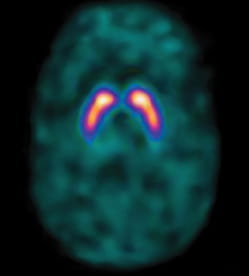

Get Spect Brain Scan Houston Texas Pics. However, in recent years, only around 110 children each year have had. Using the coveted spect brain scan at mind for life, we can find the exact places in our brain that need healing and can prescribe the right methods to improve brain function for peak performance.

Some tests, such as a single photon emission computed tomography (spect) or a positron emission (pet) scan, use radiotracers, which are radioactive substances during a brain perfusion scan using a radiotracer, your healthcare provider will inject a radiotracer into a vein in your arm. Your doctor has ordered a brain spect scan. Your doctor has ordered a brain spect scan.

The patient lies on a table that slides through the machine, while a pair of gamma cameras rotate around. Amen clinics is different because we use a brain imaging diagnostic tool called spect (single photon emission computed tomography) to help accurately identify underlying brain. We service the southwestern area including katy, sugar land, richmond, missouri city, rosenberg. What looks like a at clinics in california, washington, illinois, texas and elsewhere, doctors offer brain at the brainwaves neuroimaging clinic in houston, doctors use the scans to diagnose and choose.